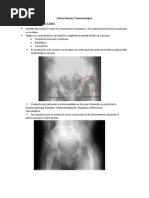

Fase inicial o de necrosis

Se produce la interrupción del aporte vascular y

necrosis ósea. En esta etapa la cabeza femoral es muy

vulnerable a las fuerzas que actúan sobre ella.

Radiológicamente existe aumento del espacio

articular (signo de Waldenström)1 secundario a una

fractura subcondral. Este es el signo radiológico más

precoz. Podemos encontrar un núcleo epifisario en la

cabeza.

Fase de fragmentación

• Se inicia un proceso de reabsorción del hueso necrótico.

• Radiológicamente aparecen densos islotes óseos, los

centrales se condensan y los laterales sufren osteólisis

produciendo una imagen atigrada.

Fase de reosificación

La densidad se desplaza en sentido contrario. La epífisis es

invadida por vasos, se reabsorben los islotes densos y se forma

tejido óseo rarefacto que luego se trabecula. Se inicia la

reparación con desaparición de la osteólisis metafisaria.